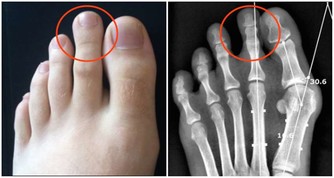

尤其需要注意的是,柚子不能和某些藥物同食:

有些病人在服用抗過敏藥特非那定期間,若吃了柚子或飲了柚子汁,輕則出現頭昏、心悸、心律失常等,嚴重的可能猝死。

同時,服用硝苯地平、維拉帕米、地爾硫卓等鈣拮抗劑,氯氮平等抗精神病藥,西沙必利等胃腸藥,環孢素A 等免疫抑製劑,咖啡因等中樞興奮劑等西藥時,不要同食柚子(汁)。